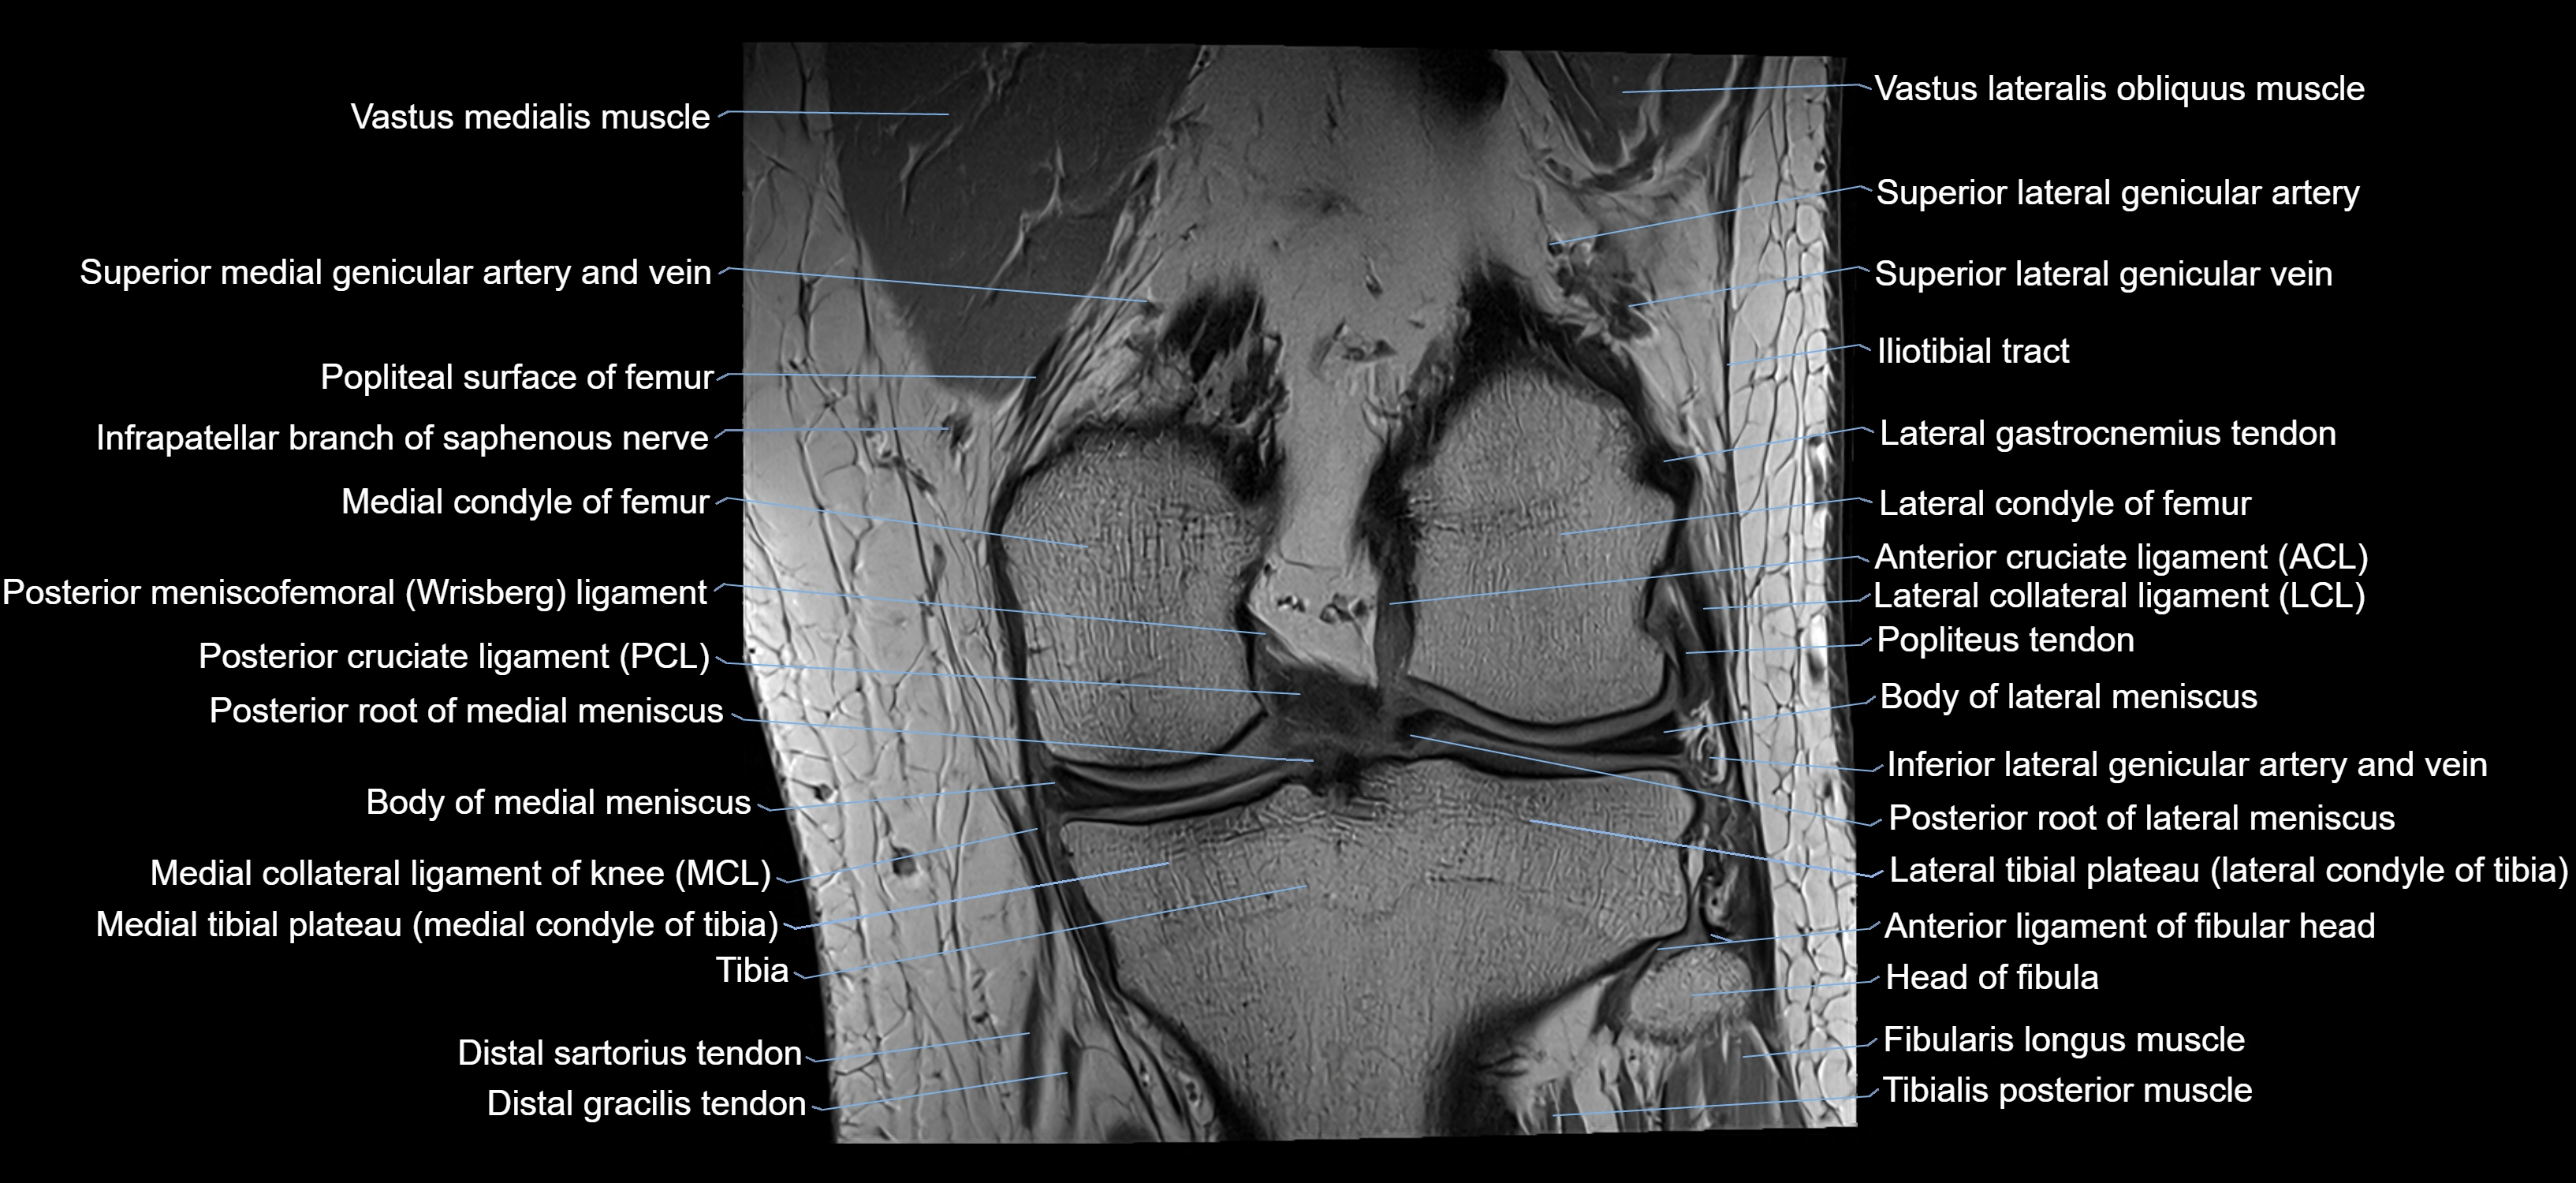

- Anterior cruciate ligament

- Anterior ligament of fibular head

- Anterolateral ligament of knee

- Body of medial meniscus

- Gracilis tendon (Distal)

- Head of fibula

- Lateral collateral ligament

- Lateral condyle of femur

- Lateral gastrocnemius tendon

- Lateral meniscus

- Medial collateral ligament

- Medial condyle of femur

- Medial condyle of tibia

- Medial meniscus

- Oblique popliteal ligament

- Popliteal lymph nodes

- Posterior cruciate ligament

- Posterior meniscofemoral ligament

- Posterior root of lateral meniscus

- Posterior root of medial meniscus

- Superior lateral genicular artery

- Superior lateral genicular vein

- Superior medial genicular artery

- Superior tibiofibular joint